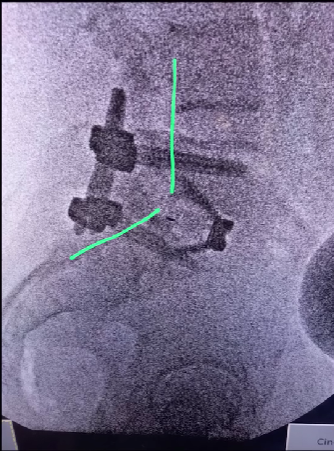

A cirurgia minimamente invasiva na coluna vertebral é um tipo de cirurgia que usa técnicas avançadas e instrumentação especializada para operar com mínima perturbação aos tecidos circundantes.

O marca-passo espinhal é geralmente considerado quando os tratamentos conservadores para a dor crônica na coluna não foram bem-sucedidos. É mais comumente usado para tratar dor crônica nas costas e nas pernas que não foi aliviada por outras terapias.